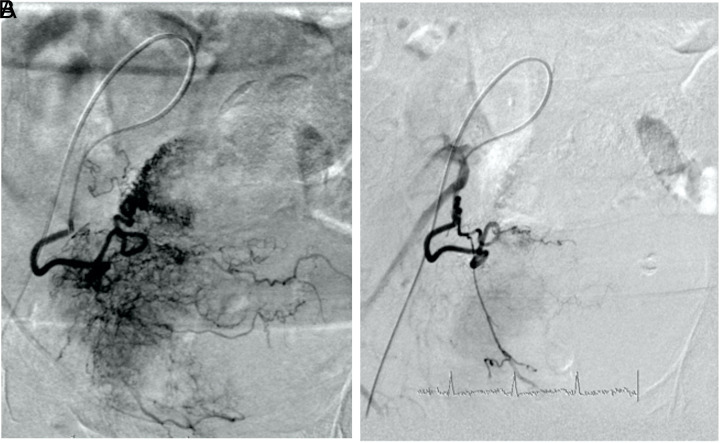

Hekimoglu, A., Ergun, O. and Hekimoglu, B. (2023). Selective Transarterial Embolization for Intractable Hematuria Due to Bladder Carcinomas: A Single-Center Experience. Urology Research & Practice, 49(5), pp.334–337. doi:https://doi.org/10.5152/tud.2023.22224.

Taha, D.-E., Shokeir, A.A. and Aboumarzouk, O.A. (2018). Selective embolisation for intractable bladder haemorrhages: A systematic review of the literature. Arab Journal of Urology, 16(2), pp.197–205. doi:https://doi.org/10.1016/j.aju.2018.01.004.